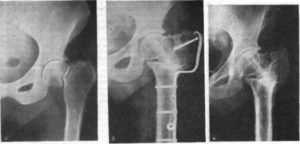

В связи с этим были предложены новые методы сращений, один из которых — метод закрытой репозиции с использованием специально разработанных конструкций в виде пластины-клинка или пластины-винта. Изделия помогают избежать экспозиции области перелома, способствуя сращению костных отломков в оптимальные сроки.

Перед выполнением операции на 3 дня применяют скелетное вытяжение для облегчения сопоставления обломков. В ходе операции применяются:

- для возрастных пациентов – динамический бедренный винт DHS;

- для более молодых или при наличии большого размера фрагментов – мыщелковые пластины:

- при многофрагментных осокольчатых переломах – эндопротезирование сустава.